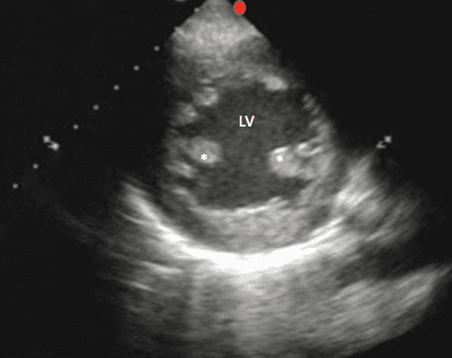

Probu çok apikal olarak havalandırmak ve papiller kaslar yerine kalbin tepesini görüntülemek (Resim 8) size sol ventrikül fonksiyonunun yanlış bir değerlendirmesine neden olacaktır.

Papiller Kaslarda ve Apekste Atel Görüntüsü PSS

* Papiller Kas Kalitesi

Apikal PSS görünümü